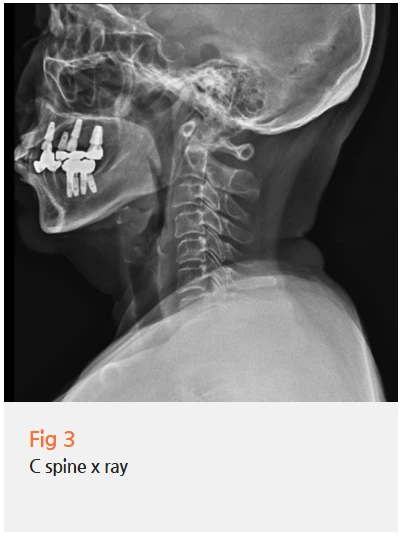

잇몸 통증뿐만 아니라 두통과 목 통증도 함께 있으셨던 거예요.

처음엔 잇몸이 너무 아파서 다른 건 신경도 못 쓰셨대요.

그런데 자세히 물어보니 목도 뻐근하고,

머리도 자주 아프다고 하시더라고요.

'아, 이거구나.'

경추 문제가 삼차신경통을 악화시키고 있을 가능성이 높았어요.

그래서 엑스레이를 촬영해 봤는데, 역시더라고요.

목에 경추 병변이 있었습니다.

목이 문제라니, 의외로 생각하실 수 있는데요.

목디스크나 일자목 같은 경추 병변이 있으면,

상부 경추 주변 근육과 후두신경이 과도하게 긴장하게 돼요.

그리고 이 후두신경과 삼차신경은 신경학적으로 연결되어 있어요.

그래서 목 문제가 삼차신경 분지에 영향을 미쳐

안면부 통증을 유발하거나 악화시킬 수 있는 거죠.

실제로 많은 삼차신경통 환자분들이 경추 문제를 동반하고 계세요.